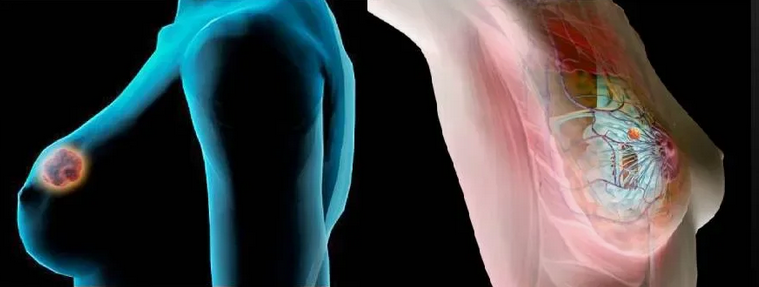

Магнитно-резонансная томография (МРТ):один из самых эффективных методов диагностики заболеваний